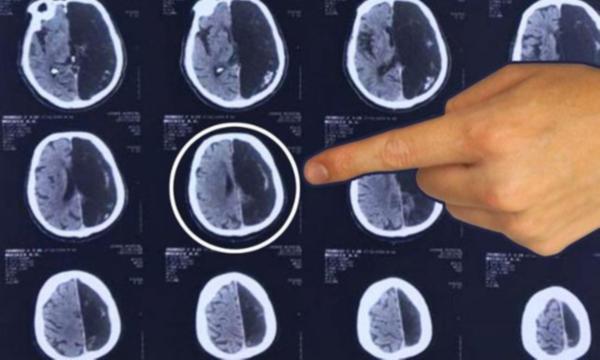

Edinilen son dakika bilgisine göre, sıradışı olaya Rusya'nın başkenti Moskova'da rastlandı. 60 yaşındaki bir emekli mühendis, "geçici iskemik atak" şikayetiyle hastaneye başvurdu.

Tahlilleri yapılan hastanın sonuçları geldiğinde beyninin yarısının olmadığı ortaya çıktı.

Doktorlar olayı şaşkınlıkla karşılarken, iki çocuk sahibi hasta "Kusursuz bir hayat yaşadım. Beni hiçbir şey rahatsız etmedi ve meşhur olmak istemiyorum" diyerek daha fazla tahlil yapılmasını reddetti.

Doktorlar, benzeri görülmemiş bu vakanın anne karnında tespit edilmesi durumunda hamileliğin sonlandırılmasını tavsiye edeceklerini söyledi.

Ancak 60 yıl önce bu durumu ortaya çıkaracak teknolojinin olmadı vurgulandı.